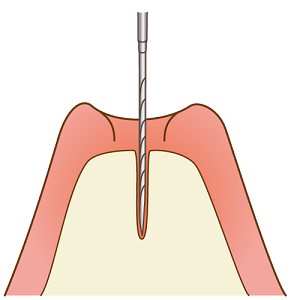

一次手術

インプラントの方向・深さを事前に検査した部分にマーキングします。

インプラントを入れる穴を専用のドリルで開けます。